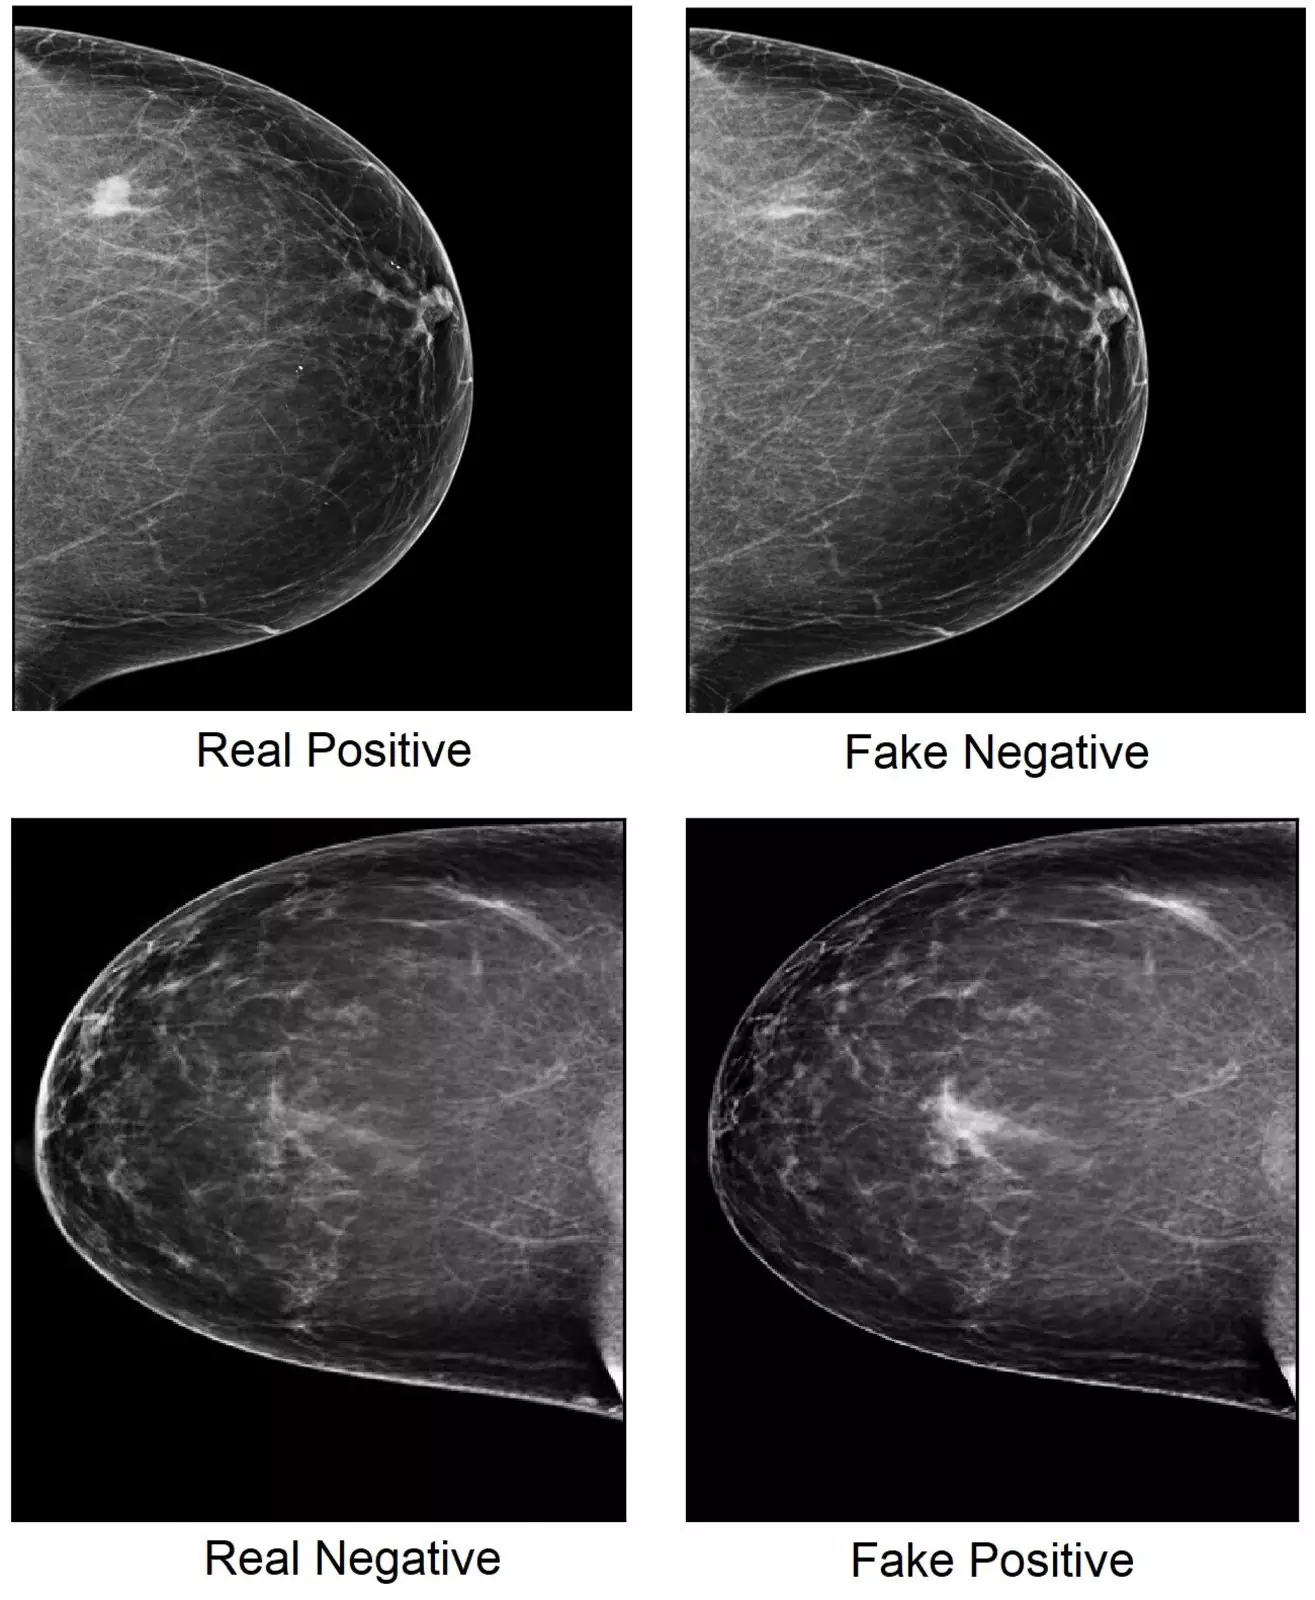

Кибератаки изменяют крошечные области изображений, которые влияют на решение ИИ, но незаметны для человеческого глаза. Это может привести к постановке ложноположительных диагнозов, — например, рака груди.

Враждебная программа при помощи манипуляций с крошечными областями пометила изображения как ложноотрицательные и ложноположительные.